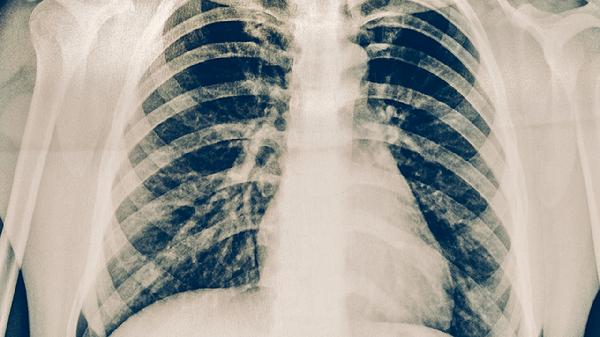

需复查胸部CT评估肺部病灶吸收情况,若病灶吸收不佳可能需延长强化期治疗。纤维支气管镜检查可明确是否合并支气管结核,支气管结核会导致气道狭窄、溃疡,表现为顽固性咳嗽。结核菌素试验、γ-干扰素释放试验等可辅助判断结核活动性。